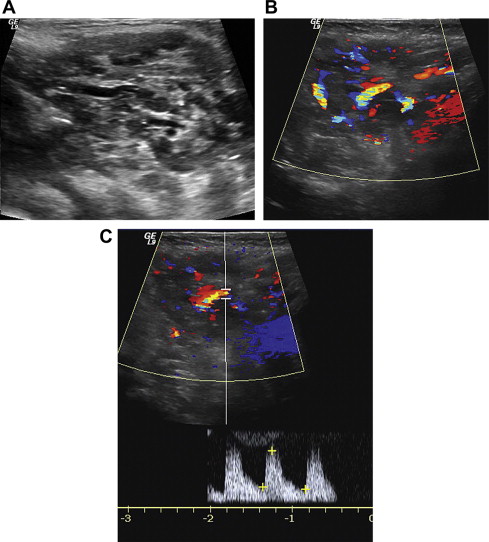

Typical ultrasonographic appearance of an infantile hemangioma, both in the proliferating stage as well as the involuting stage, is a well-circumscribed hypervascular mass showing low-resistance arterial waveforms ( Fig. 1 ). Most hemangiomas are hypoechoic, although up to 18% have been reported to be hyperechoic. Hemangioma can be differentiated from arteriovenous malformations (AVMs) by the presence of solid parenchymal tissue.